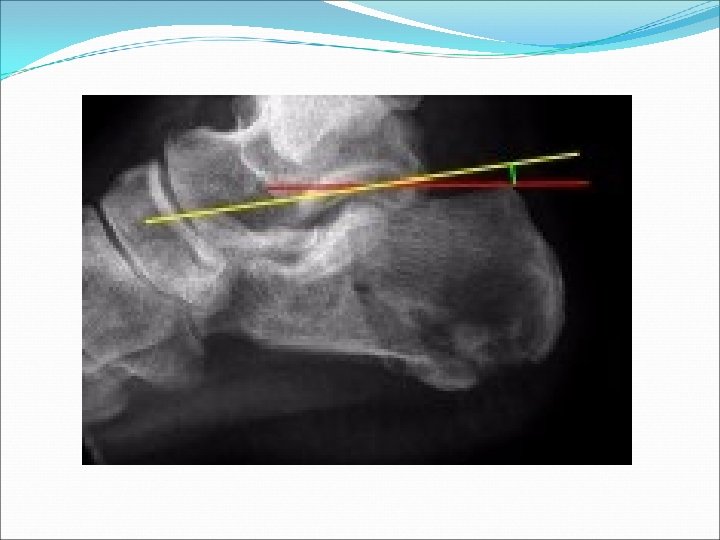

R calcaneus x-ray:

Bohler’s angle (30 -40 deg)